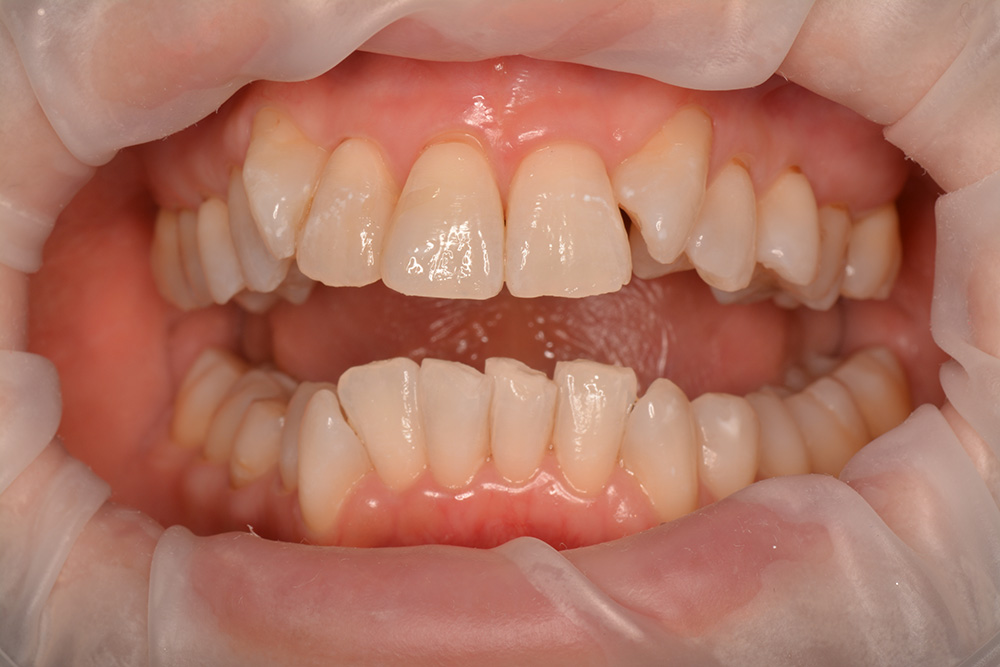

術前

世代・性別

40代女性

主訴

歯が揺れている気がするので見てほしい

治療内容

ブラッシング指導、歯周基本治療

治療期間

4ヶ月

治療費

保険適応内

治療のリスク

一時的に歯ぐきからの出血や痛み、歯のしみ(知覚過敏)が起こることがある